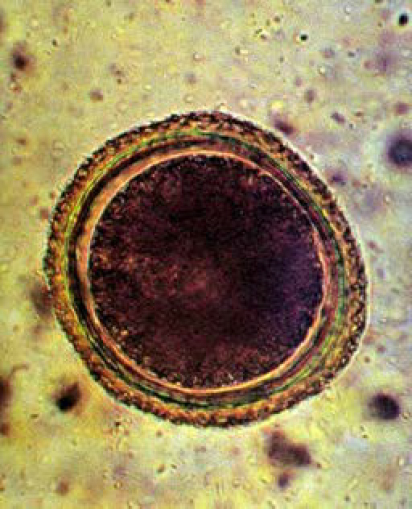

Микрофотографии яиц гельминтов Toxocara canis

Раздел: Фотоэссе